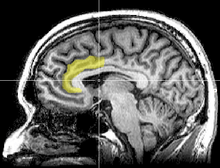

Using functional magnetic resonance imaging (fMRI), Van Veen and colleagues investigated the neural basis of cognitive dissonance in a modified version of the classic induced compliance paradigm. While in the scanner, participants "argued" that the uncomfortable MRI environment was nevertheless a pleasant experience. The researchers replicated the basic induced compliance findings; participants in an experimental group enjoyed the scanner more than participants in a control group who simply were paid to make their argument.[64]

Importantly, responding counter-attitudinally activated the dorsal anterior cingulate cortex and the anterior insular cortex; furthermore, the degree to which these regions were activated predicted individual participants' degree of attitude change. Van Veen and colleagues argue that these findings support the original dissonance theory by Festinger, and support the "conflict theory" of anterior cingulate functioning.[64]

Subsequent fMRI studies, also using the free choice paradigm, have examined the decision-making process in the brain. A 2010 study showed that during decision-making processes where the participant is trying to reduce dissonance, activity increased in the right-inferior frontal gyrus, medial fronto-parietal region and ventral striatum, whereas activity decreased in the anterior insula.[67] Researchers concluded that rationalization activity may take place quickly (within seconds) without conscious deliberation. In addition, the researchers stated that the brain may engage emotional responses in the decision-making process.[67]

Cognitive dissonance has been associated with left frontal activity in the cortex (Harmon-Jones, 1999 and Harmon-Jones and Harmon-Jones, 2002). In addition, the left frontal cortex has been associated with anger, with anger supporting a motivational purpose behind its anger showing the left frontal activity being active. Together, cognitive dissonance and anger are supported with the motivational directional model. Approach motivation is associated with the left frontal cortex when it can be detected that a person may able to take control of a situation that may have made them angry. Conversely, if a person does not have control of changing the situation, then there is no motivation involved and other emotions may arise.[60][68][69]

The anterior cingulate cortex activity increases when errors occur and are being monitored as well as having behavioral conflicts with the self-concept as a form of higher-level thinking (Amodio et al., 2004). A study was done to test the prediction that the left frontal cortex would have increased activity. University students had to write a paper depending on if they were assigned to a high-choice or low-choice condition. The low-choice condition required student to write about supporting a 10% increase in tuition at their university. The point of this condition was to see how significant the counterchoice may affect a person's ability to cope. The high-choice condition asked students to write in favor of tuition increase as if it was their choice and that it was completely voluntary. EEG was used to analyze students before writing the essay as dissonance is at its highest during this time (Beauvois and Joule, 1996). High-choice condition participants showed a higher level of the left frontal cortex than the low-choice participants. Results have shown that the initial experience of dissonance can be apparent in the anterior cingulate cortex, then the left frontal cortex is activated, which also activates the approach motivational system to reduce anger.[70][71]